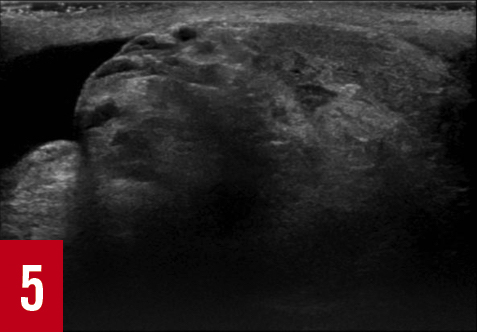

At 4 hours after the onset of pain, testicular ultrasonography was performed in view of the persistent mild left testicular tenderness noted during the initial examination. The results revealed left testicular torsion with an absence of blood flow to the left testis (Figures 1-5). The scrotal skin was of normal thickness with no hyperemia. The testis demonstrated normal size and echogenicity, but the epididymal head was enlarged and ill-defined, with prominent cystic features indicative of infarction. A small hydrocele was also present. The spermatic cord was normal, with no signs of torsion in the inguinal canal.

Figure 5: Left epididymis was enlarged with cystic lesions.